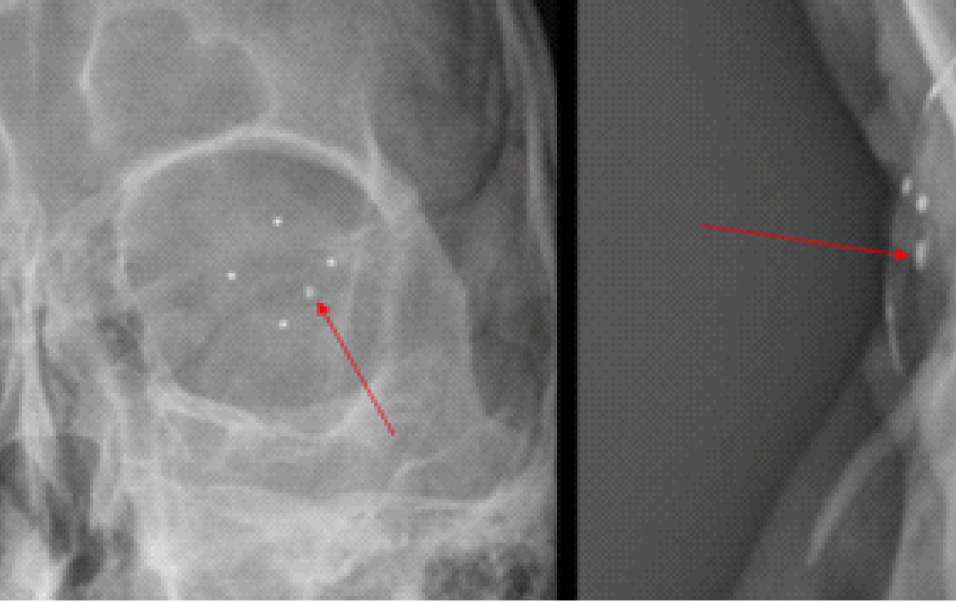

Пациенту был проведен комплекс инструментальных исследований, включающий в себя ультразвуковое исследование (УЗИ) и ультразвуковую биомикроскопию (УБМ), рентгенографию глазниц (РГ) с локализацией инородного тела по методу Комберга – Балтина, компьютерную томографию (КТ) головы. Эхографическая картина заднего сегмента OS имела следующие особенности: витреоретинальные тяжи, мелкодисперсная взвесь – выпот, хрусталик люксирован в стекловидное тело, нельзя исключить ВГИТ на глазном дне. УБМ выявила инородное тело в передней камере по меридиану 4–5 часов (рис. 2). При рентгенографии OS по Комбергу – Балтину определялось ВГИТ размерами 2 × 1 × 1 мм, по меридианам 4 часа 10 минут – 4 часа 40 минут, на расстоянии 4 мм от анатомической оси глаза, на расстоянии 1–2 мм от плоскости лимба (3–4 мм при пересчете на склеру) (рис. 3).

Рис. 3. Рентгенография по методу Комберга – Балтина. ВГИТ указано стрелкой